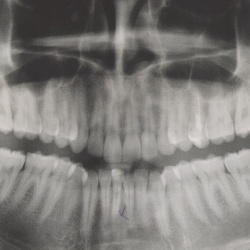

Добрый день. Три года назад была травма челюстно-лицевого сустава справа. Был нанесен удар по челюсти, после этого она начала щелкать. В больнице сказали что нужно менять прикус для исправления...